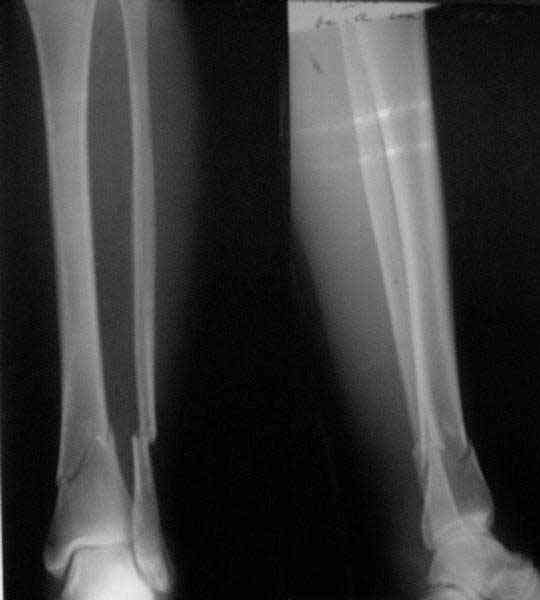

A typical case is attached, also an image with intra-op reduction obtained by a small wire distractor, in the moment of insertion a Poller wire in AP direction. Fixation by a SIGN nail. Despite the fibula was not fixed healing was obtained with the unchanged alignment.

[ Ответить ]

Отправитель: T. Derek V. Cooke 21 Май 2006, 23:18

Alex:

Very interesting application, but is the final position in a little distal varus with some fibula

distraction? Would that have been eliminated by fibula plating?

Отправитель: Alexander Chelnokov 21 Май 2006, 23:21

TDVC> Very interesting application, but is the final position in a

TDVC> little distal varus with some fibula distraction?

At least both the ankle mortise and tibial alignment look acceptable, don't they?

TDVC> Would that have been eliminated by fibula plating?

I am just trying to illustrate that prevention of 1)tibial valgus and 2)loss of reduction can be provided without fibular plating. Small changes of conventional nailing techniques allow to maintain reduction of the tibia reliably without adjunctive fibular stabilization.

In delayed cases acute length restoration performed only in the tibia may leave the fibula shortened thus change the mortise. So it is reasonable to restore length of both bones simultaneously by distractor and fix the fibula not with open reduction and plating but just by a single perQ screw. Example attached.